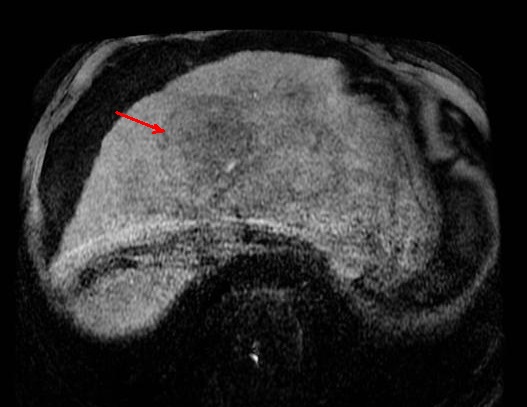

Image IRM enT1 du

carcinome hepatocellulaire : Aspect lesionaire

est isointense du foie droit ( fleche rouge ) . Foie

est en cirrhose , ascitique |